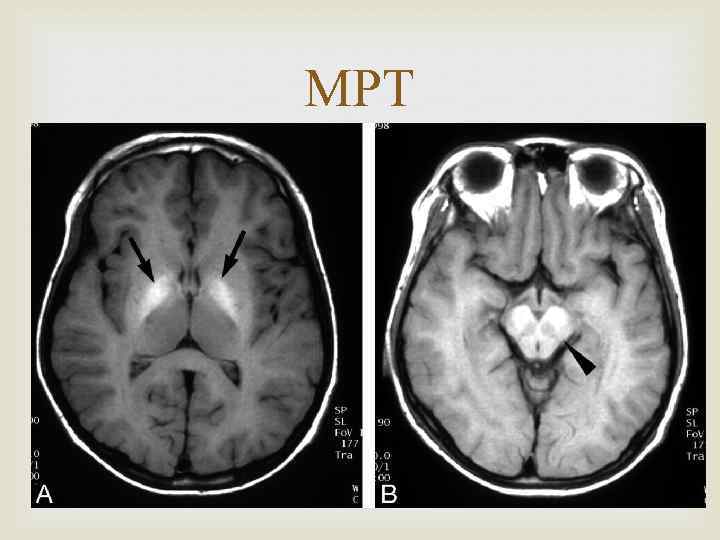

МРТ